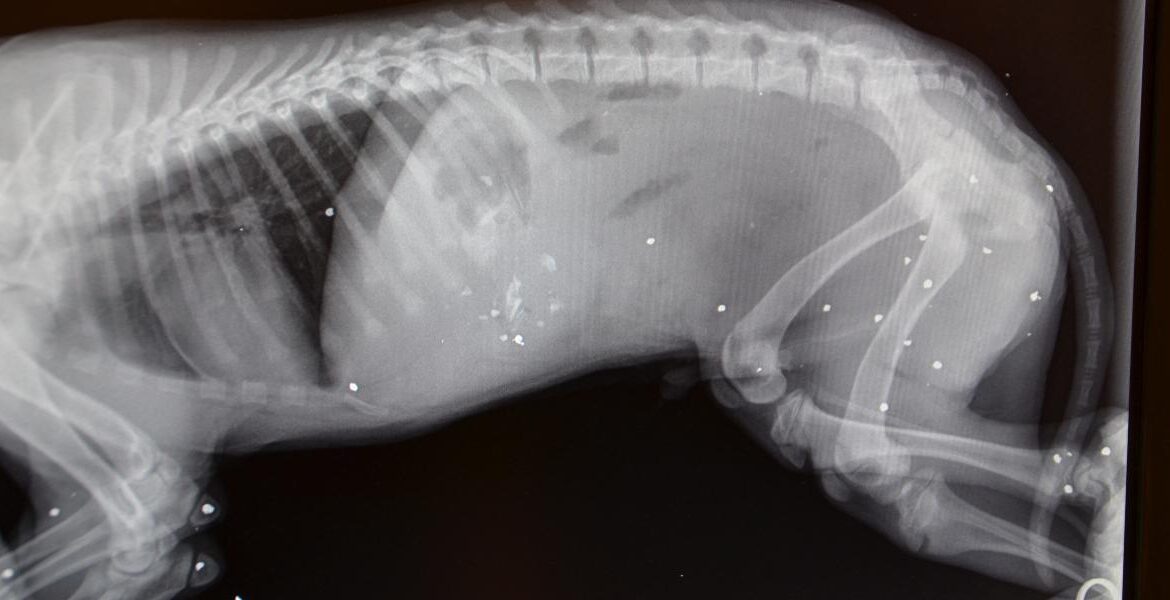

Ενημερώστε τον αξιότιμο πρωθυπουργό μας ότι στην Τήνο, όπου διατηρεί εξοχικό, ο σκύλος του μπορεί να βγάλει ακτινογραφία αν χρειαστεί, ενώ οι Τηνιακοί πολίτες θα πρέπει να ταξιδεύουν Μύκονο ή Σύρο”. Με αυτά τα λόγια ξεκινάει η αφήγηση ενός διαδικτυακού φίλου, αγαπητού κτηνίατρου στην Τήνο, που περιγράφει την αμήχανη και δύσκολη θέση στην οποία βρέθηκε εσχάτως, καθώς τις πρώτες μέρες του 2022 δέχεται εκκλήσεις από συντοπίτες του να βγάλουν ακτινογραφίες στο μηχάνημα με το οποίο είναι εξοπλισμένο το κτηνιατρείο του, αφού το ακτινολογικό στο Κέντρο Υγείας του νησιού για ακόμη μία φορά δεν λειτουργεί.

Σε μια κρίσιμη για τη δημόσια υγεία περίοδο, που η ακτινογραφία θώρακα είναι αυτή που καθορίζει το θεραπευτικό πλάνο για τα περιστατικά Covid, οι κάτοικοι της Τήνου έχουν μείνει χωρίς ακτινολογικό μηχάνημα και παρακαλούν για μια ακτινογραφία σε ένα κτηνιατρείο. Για τέτοια χώρα μιλάμε και για τέτοιο επιτελικό κράτος. Μια χώρα που ζει και υποφέρει πίσω από τη βιτρίνα με τα μεγάλα λόγια της ανάπτυξης, των επενδύσεων, της ευημερίας και της τεχνολογικής επανάστασης. Μια χώρα που ζει και υποφέρει δίπλα σε ένα από τα πολλά εξοχικά του πρωθυπουργού. Μια άλλη Ελλάδα, που καμία σχέση δεν έχει με τα δελτία ειδήσεων..